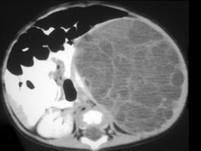

问题 男,5岁,左季肋部可触及一包块,请根据其影像,选择最可能的诊断 ( )

选项 A、左肾细胞癌 B、左肾多房性囊肿 C、左肾单纯性囊肿 D、左肾脓肿 E、左肾血管平滑肌脂肪瘤

答案 B